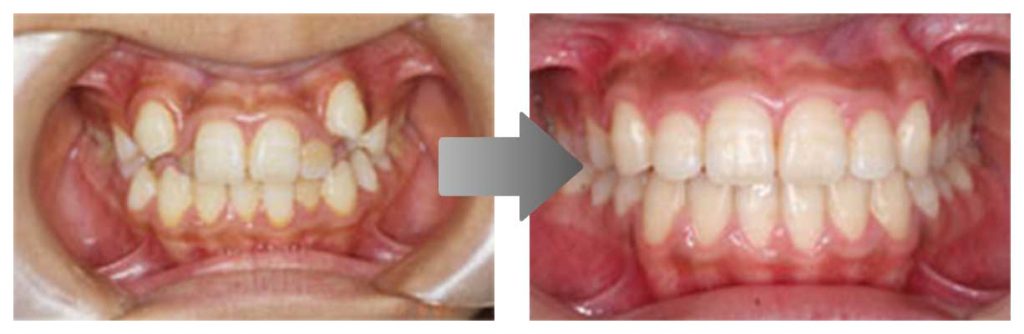

矯正の症例

3) 矯正を終えた状態

叢生(そうせい…歯がデコボコしたり、重なりあって生えていたりする状態)

開咬(かいこう…奥歯はしっかり噛んでいるが、上下の前歯が噛まずに隙間がある状態)